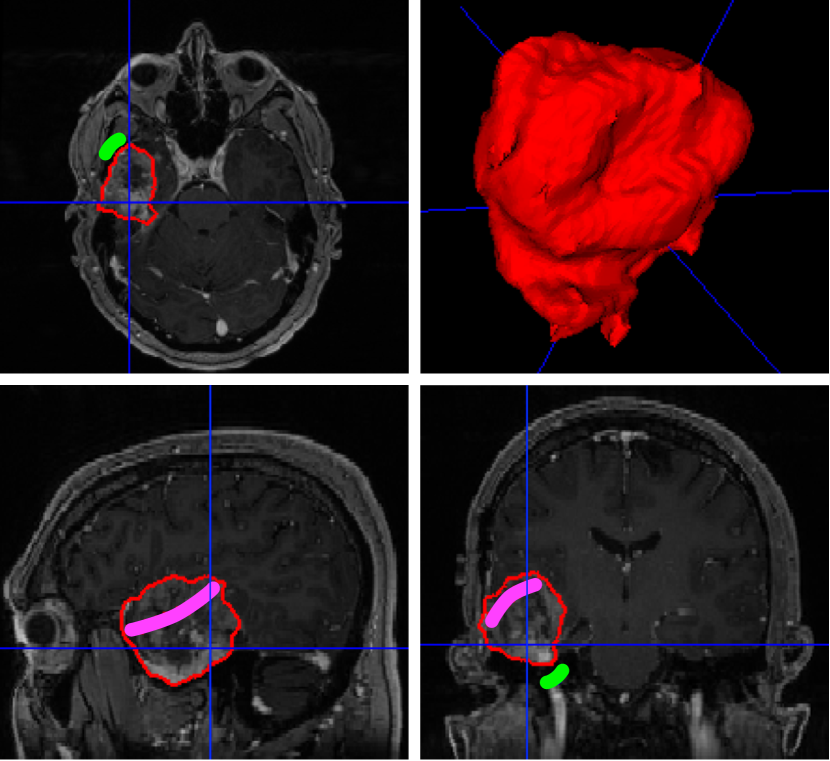

What distinguishes segmentation in surgical planning from segmentation in diagnostic imaging is nonetheless that the objective is not necessarily always that of reaching the best performance in getting the structures delineated with sub-voxel accuracy. Surgical planning needs to respect patient-specific needs and preferences of the surgeon. This requires putting the clinical team at the centre and promoting flexible tools that integrate into the surgical workflow. Interactive deep learning methodologies are emerging to combine rich prior knowledge embedded in retrospective data from previous patients with as-sparse-as-possible annotations provided by clinicians [18, 8]. As illustrated in Figure 1, deep interactive segmentation allows the clinical expert to refine the results from an initial automated step and most importantly to adapt the inferred results on the fly based on contextual information. Furthermore, given the heterogeneity and evolving nature of surgical practice, additional flexibility is required to handle potentially missing input modalities. Recent work in deep machine learning are focusing on dealing with such dynamic hetero-modal context while exploiting heterogeneous sources of data for the training process [19, 20]. Bringing flexible machine learning tools to maturity will certainly play an important role in supporting the clinical adaption of AI in surgery.